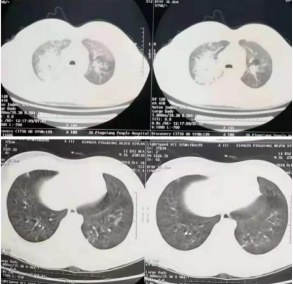

新冠肺炎患者肺部ct图

国际首例,新冠病毒肺炎危重症患者病理活检报道

美国医院vr影像展示新冠肺炎患者肺部肺损伤或

新冠肺炎的肺ct图片

新冠肺炎肺部影像

新冠肺炎ct表现

新冠肺炎ct

新冠肺炎ct影像